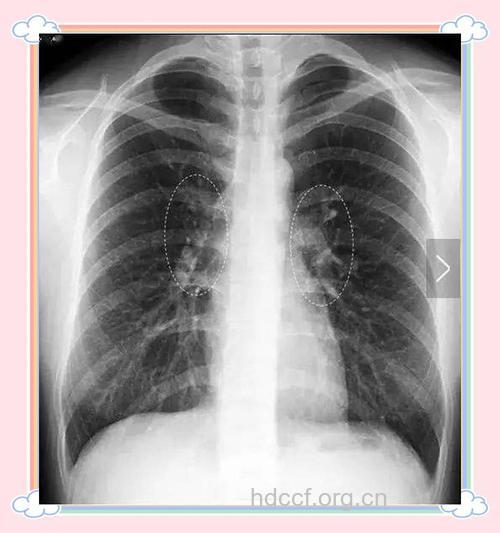

肺部阴影,是指在X线胸片、胸部CT等影像学检查中所发现的片状或肿块影。一般来说,会表现为“肺部阴影”的疾病,除了有肺癌、肺部先天性发育异常之外,比较多见的还有肺部感染性疾病,包括肺炎、肺结核、支气管扩张、肺曲霉菌病等。

其中,细菌导致的慢性肺炎最为常见,除了检查中发现有肺部阴影外,患者还常有咳嗽、咳痰、发烧、胸闷、乏力、呼吸困难等症状,肺部阴影在胸片上往往呈片状。应用抗生素治疗后复查胸片,会发现肺部阴影明显缩小,甚至完全消失。

肺结核是结核杆菌造成的肺部感染,患者常有咳嗽、咳痰和咳血以及午后低热、乏力、盗汗、食欲减退等结核中毒症状。如果在痰液里查到抗酸杆菌,皮肤结核菌素试验呈强阳性,就可以确诊。多数肺结核患者在应用抗结核药物治疗后就可康复。

医生指出,如果在X线片检查中发现“肺部阴影”,人们不必过分紧张,但应立即去正规医院进行系统的检查。低剂量的胸部CT扫描检查是初步筛查肺癌的最佳办法之一,专业医生会通过影像学检查结果综合患者的症状来判断病情。